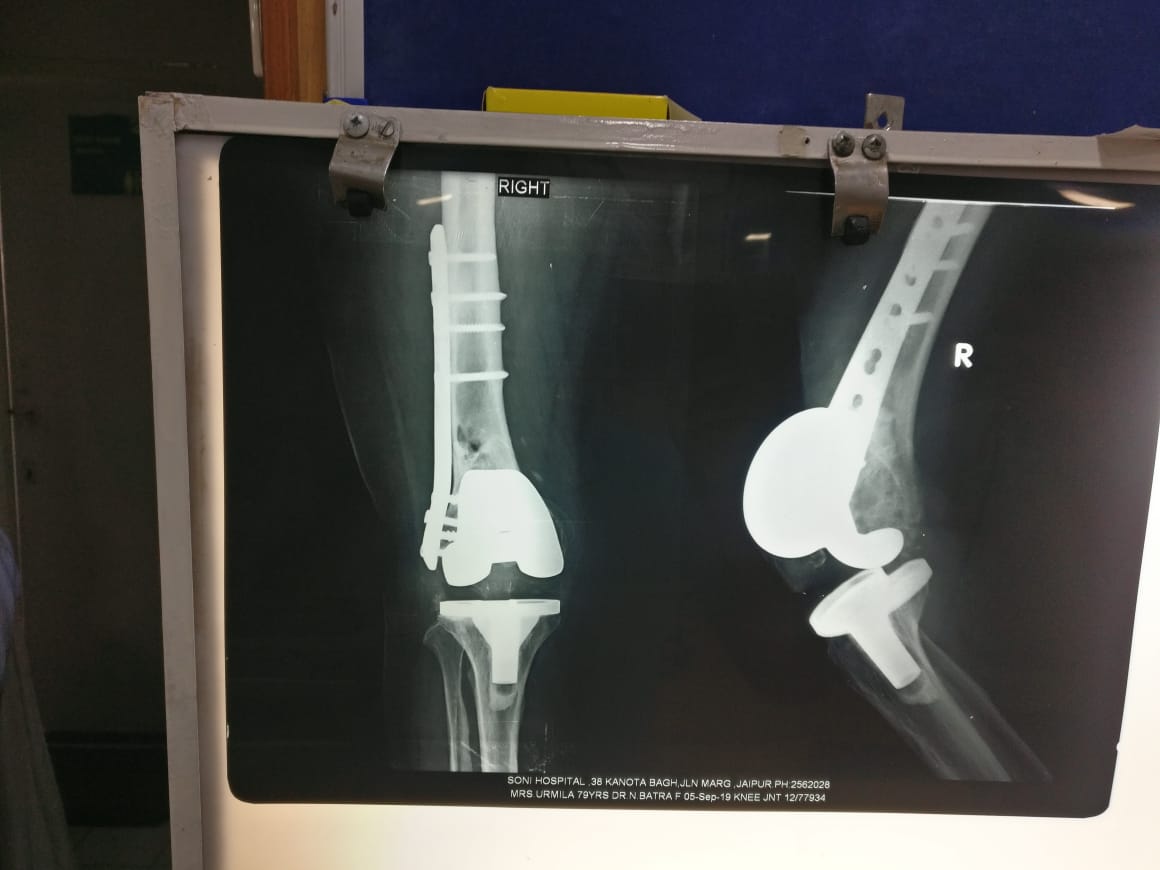

Knee Replacement ( oprated 12 Years Back)

Knee rplacement after 5 year